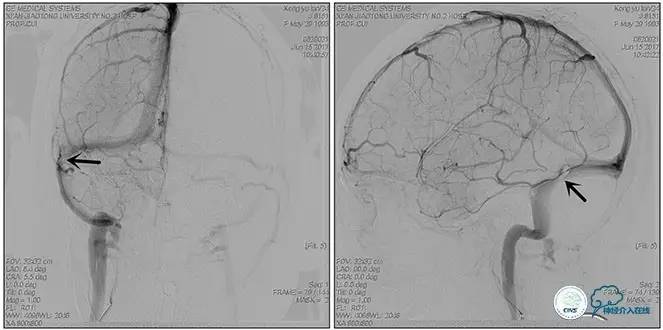

右侧ICA造影正侧位

右侧ICA造影斜位

右侧ICA正侧位

右侧ICA斜位

静脉淤滞